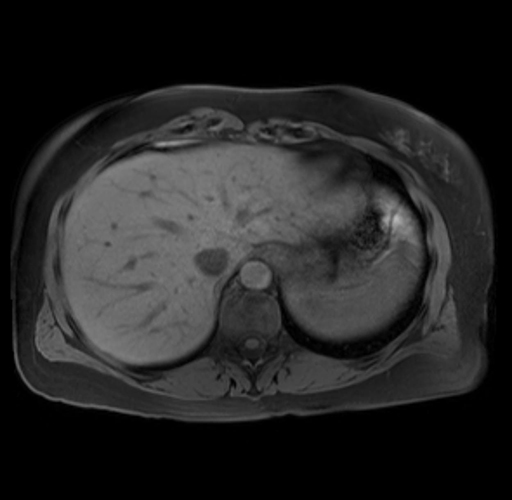

Imaging Analysis

Look through the patient's CT scan to identify any areas of concern for the necessary procedure.

Based on your CT findings, which issue(s) are present and would give reason for "planned slowing down moment(s)" in this case?